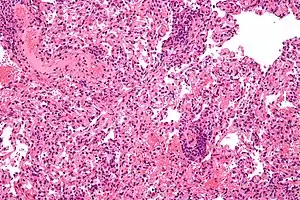

![]() | |

| Micrograph showing lung transplant rejection. Lung biopsy. H&E stain. | |